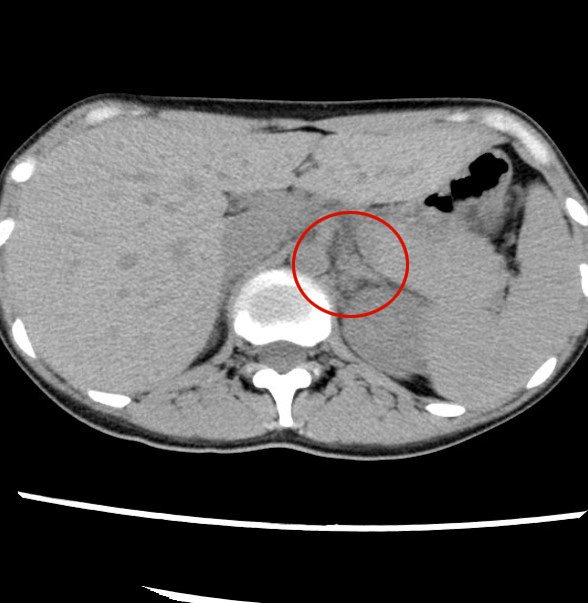

- 【1週間後 単純CT】

- 右副腎の腫大

- 右副腎周囲の脂肪織濃度上昇

- 左副腎の腫大は軽減